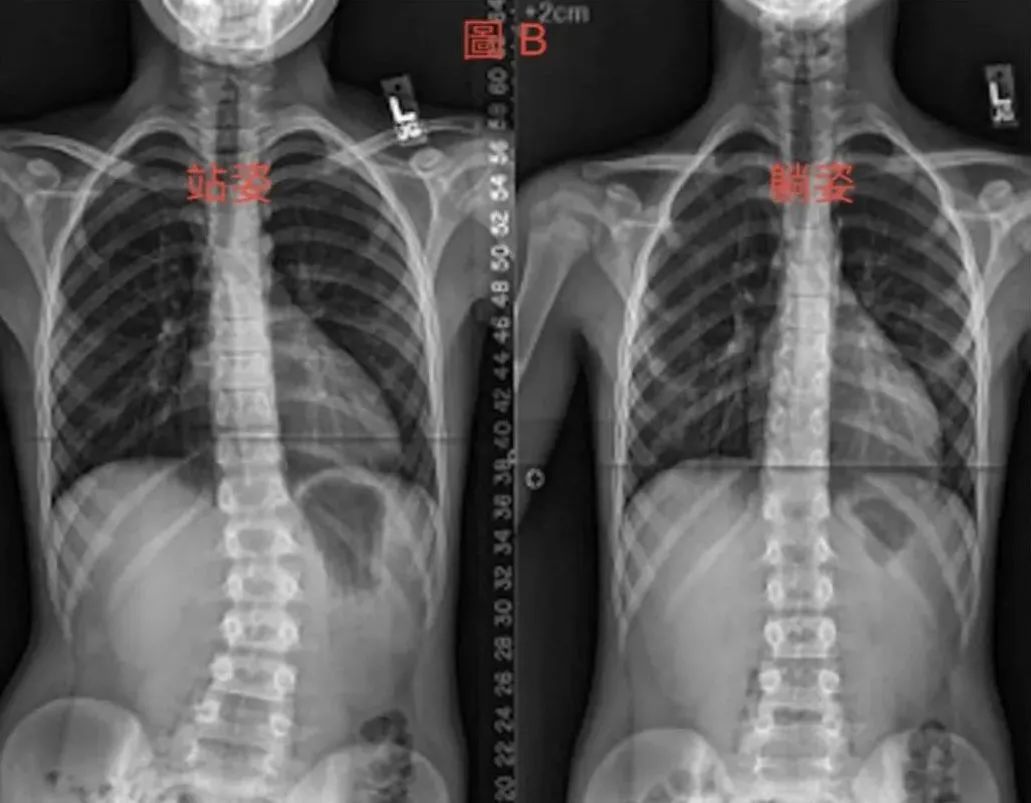

这类型脊柱侧弯大多数因为脊柱受伤过,导致肌肉紧绷、或是骨盆歪斜、以及长短脚等因素使得身体因为疼痛姿势而引起的弯曲。此类的脊柱侧弯,脊柱本身没有任何的问题。因此只要有效的针对弯曲的角度做治疗或调整,便能有效的改善弯曲度数。我们可以通过运动以及姿势训练及关节矫正等非侵略性,较温和的方式来治疗改善。

由X光片可以看出功能性的脊柱侧弯在站姿下(左图),因为脊柱需要对抗重力,因此会因为脊柱两侧肌肉不正确出力而产生曲度,但在非抗重力的躺下(右图)脊柱就又会呈现直立的正确姿势了。此类的脊柱侧弯患者脊柱本身并没有问题,只需要学习如何控制肌肉的力量便可改善。